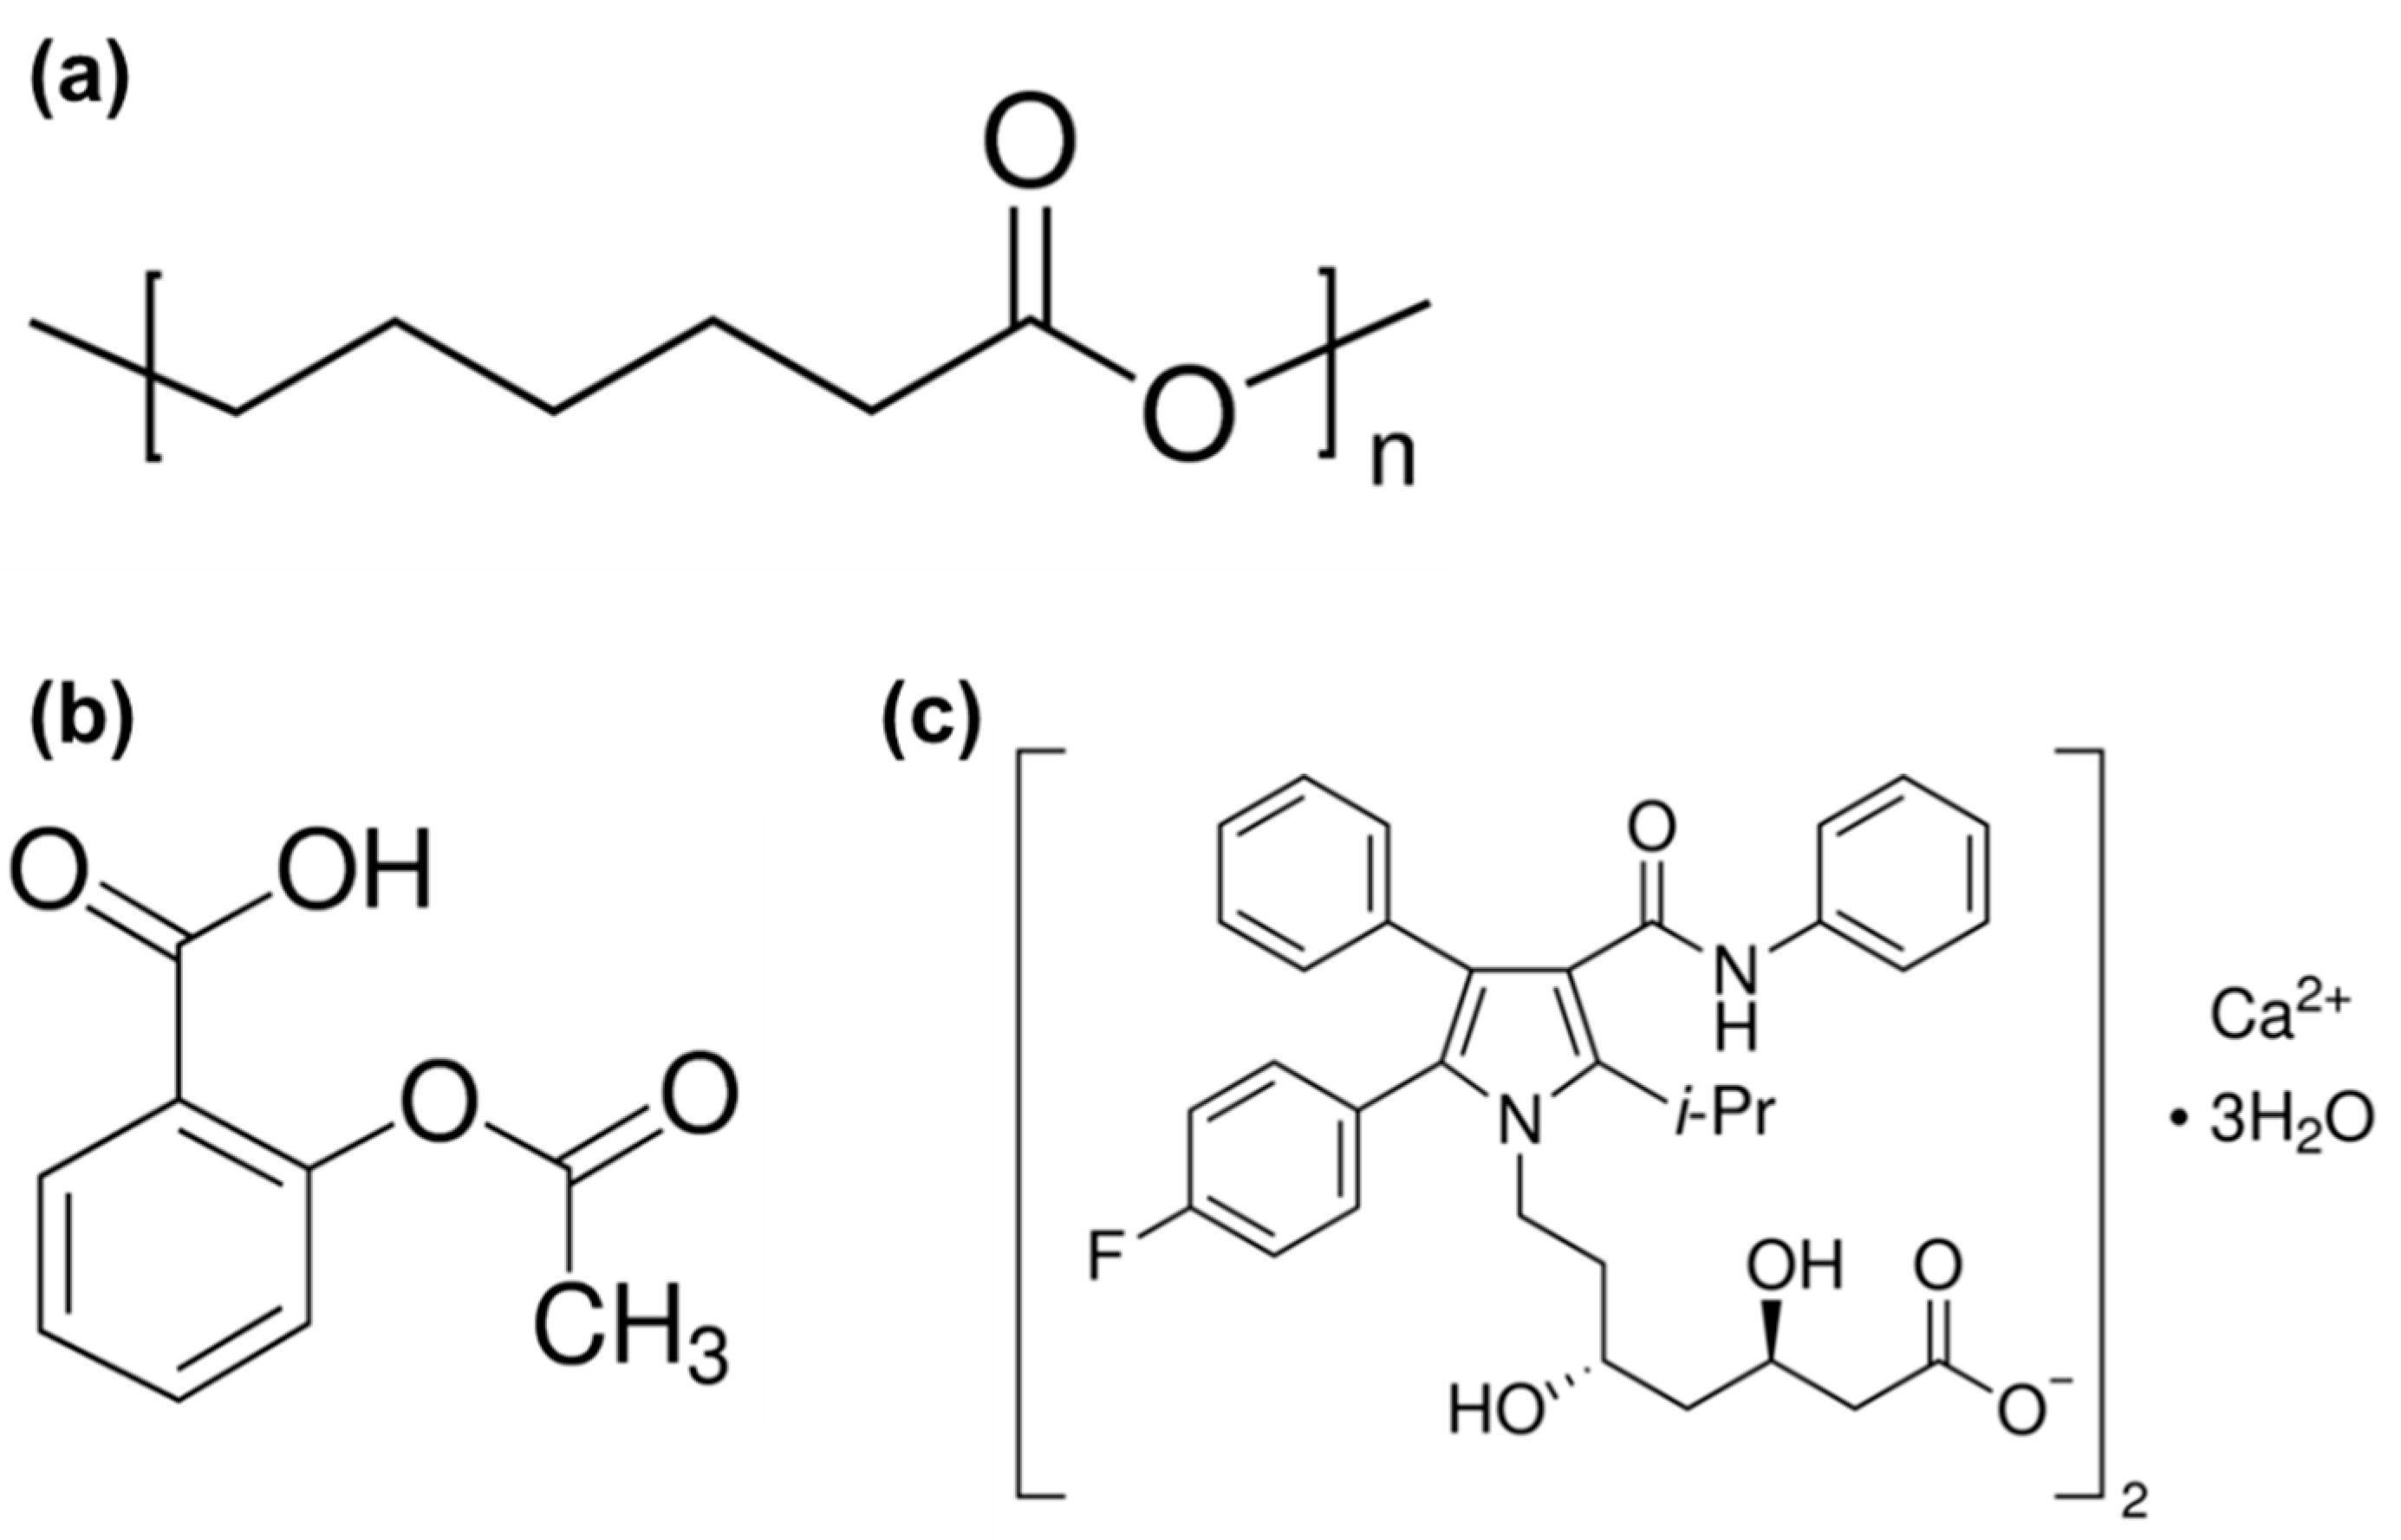

2.1. Materials

2.3. Preparation of the Atorvastatin Calcium Salt: Aspirin Stock Solutions

2.4. Drug Coating on the Porous PCL Scaffolds